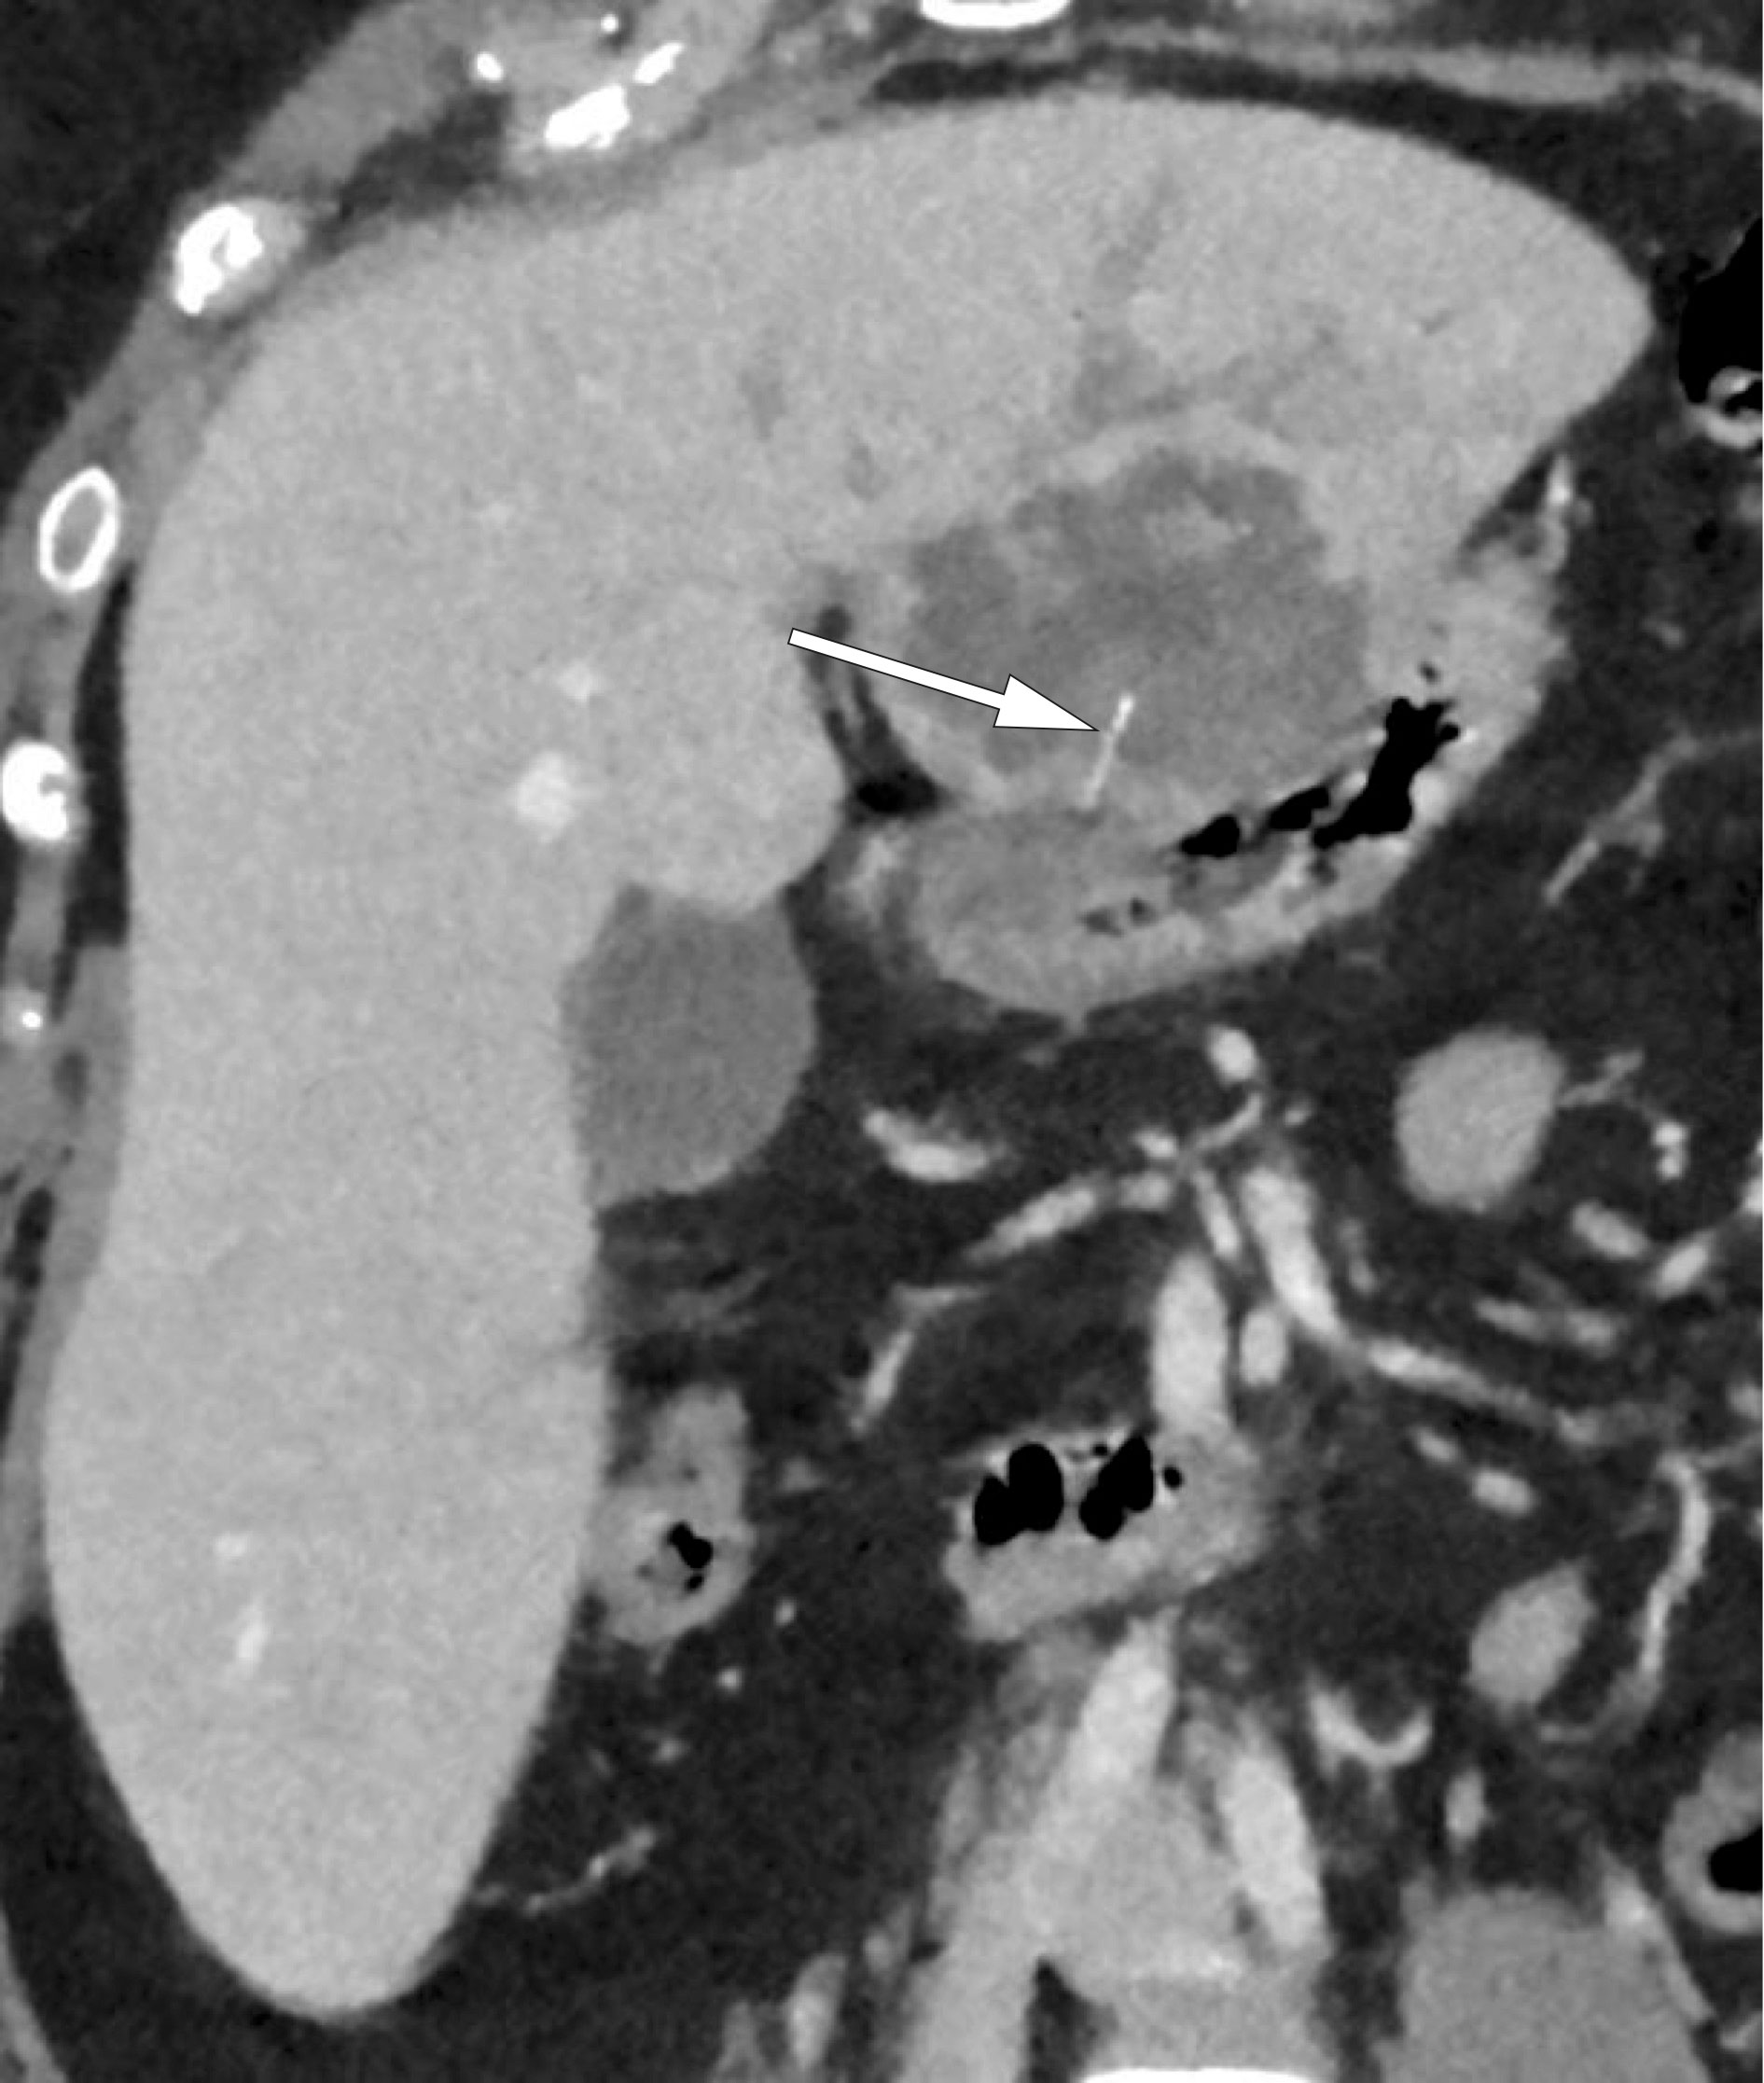

Det kliniske bildet ble tolket som sepsis, og intensiv intravenøs væskebehandling og bredspektret intravenøs antibiotika (piperacillin 4 g/tazobaktam 0,5 g × 3 daglig) ble startet opp. Computertomografi (CT) av abdomen (figur 1) viste en stor lesjon i venstre leverlapp på 6,3 × 6,1 × 6,4 cm, som ble tolket som en primær leverabscess.

En ny granskning av CT-undersøkelsen påfølgende dag vakte mistanke om et fremmedlegeme i relasjon til leverabscessen. Fremmedlegemets tetthet og utseende kunne passe med et fiskeben. Klinisk mistenkte man perforasjon fra ventrikkelen. Ultralyd, som ble utført i forbindelse med anleggelse av dren til abscessen, bekreftet mistanken om et fremmedlegeme (figur 2). Det kom spontant blodtilblandet pusslignende væske på drenet, og man sikret prøver for bakteriologisk bestemmelse. Gastroskopi dagen etter viste normale forhold, og man så ingen mulighet for å fjerne fremmedlegemet.